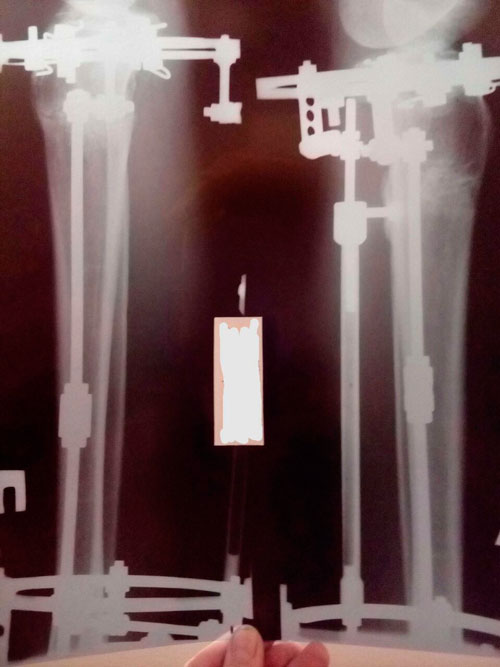

Ножки рентген в 90 дней.

IMG-20171223-WA0001.jpg

IMG-20171227-WA0053.jpg

IMG-20171227-WA0052.jpg